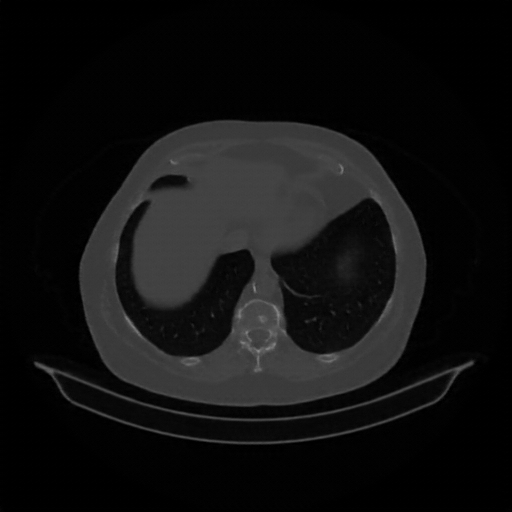

Slice 70 Targeting Evaluation

Slice: Slice_70

Conversion: NATIVE β†’ VENOUS

Targeted Slice 70 - Mediastinum Window Analysis (Generated vs Real Venous)

0.807

Mediastinum SSIM

37.0

Mediastinum RMSE

13.2

Mediastinum MAE

Generated VENOUS CT scan (A→B translation)

Mediastinum window (WL 40, WW 400 β†’ Low βˆ’160, High +240)

Reconstructed NATIVE CT scan (cycle consistency)

No window - Raw intensity values